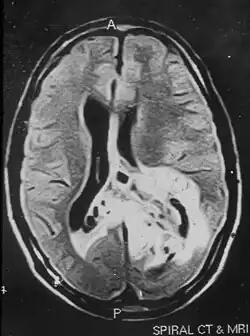

Brodawkowaty nowotwór glioneuronalny (ang. papillary glioneuronal tumor, PGNT) – niedawno opisany pierwotny złośliwy guz ośrodkowego układu nerwowego, uwzględniony w najnowszej klasyfikacji WHO (2007)[1]. Opisano mniej niż 40 przypadków pacjentów z PGNT. PGNT występuje równie często u mężczyzn i kobiet, opisywano go w różnych grupach wiekowych (wiek zachorowania od 4 do 75 lat; średnio 28 lat). Najczęstszą manifestacją nowotworu są padaczka (lokalizacja w płatach czołowych), w innych lokalizacjach objawy są niespecyficzne (ból głowy); nie opisywano objawów ogniskowych. Jest guzem mieszanym, histologicznie PGNT zawiera komponenty glejową i neuronalną, charakteryzuje się pseudobrodawkowatym typem wzrostu i hialinizacją naczyń guza. Uważany jest za guz o niskim stopniu złośliwości. PGNT został opisany w 1998 roku przez Komoriego i wsp.[2].